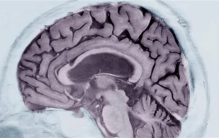

新技术:核磁共振扫描即可确诊阿兹海默症

科学家发明了一套机器学习系统,用这套系统只需分析问诊者的一次脑部核磁共振(MRI)扫描的数据,即可判断其是否患有阿兹海默症。研究者称准确率高达98%。 阿兹海默症(Alzheimers)是失智症中最常见的一种,发病者多为6 ...